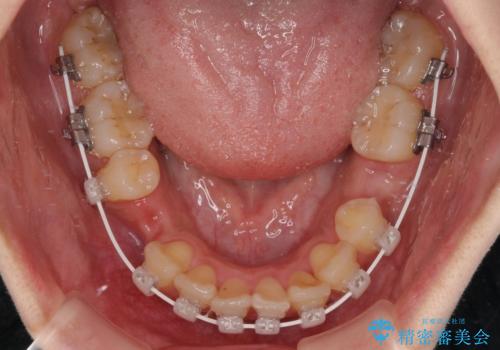

- 審美装置

- 1年11ヶ月

アンカースクリューと補助装置を使用して上顎大臼歯を遠心移動させることで咬み合わせを改善し、更には口元の突出感を改善するために上下左右の小臼歯4本を抜歯し、ワイヤー装置によりデコボコを解消しながら口元の突出感も改善していくこととしました。